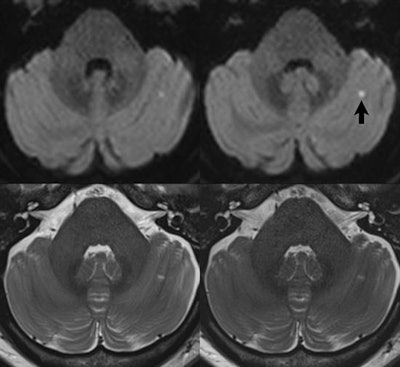

The use of simultaneous multislice imaging to decrease scan time for thin section imaging of the brain. A small pinpoint early subacute cerebellar infarct (arrow) is seen, on images acquired at 3-tesla using a 64-channel head and neck coil, in a 49-year-old female patient. For all scans, 2.5-mm-thick sections were acquired through the entire brain. Readout-segmented, diffusion-weighted (b = 1,000) images are compared in the upper row, without and with simultaneous multislice imaging (two times acceleration). simultaneous multislice imaging was used to allow a decrease in TR from 12.75 to 6.38 seconds, with scan time thus decreasing from 5:46 to 3:26min:s. In the lower row, T2-weighted scans without and with simultaneous multislice imaging (three times acceleration) are compared. In this instance, simultaneous multislice imaging was used to eliminate the need for concatenations (three were required for the conventional scan, due to the number of slices), resulting in a decrease in scan time from 1:29  3 (4:27) to 1:45 min:s.The use of simultaneous multislice imaging to decrease scan time for thin section imaging of the brain. A small pinpoint early subacute cerebellar infarct (arrow) is seen, on images acquired at 3-tesla using a 64-channel head and neck coil, in a 49-year-old female patient. For all scans, 2.5-mm-thick sections were acquired through the entire brain. Readout-segmented, diffusion-weighted (b = 1,000) images are compared in the upper row, without and with simultaneous multislice imaging (two times acceleration). simultaneous multislice imaging was used to allow a decrease in TR from 12.75 to 6.38 seconds, with scan time thus decreasing from 5:46 to 3:26min:s. In the lower row, T2-weighted scans without and with simultaneous multislice imaging (three times acceleration) are compared. In this instance, simultaneous multislice imaging was used to eliminate the need for concatenations (three were required for the conventional scan, due to the number of slices), resulting in a decrease in scan time from 1:29  3 (4:27) to

1:45 min:s.